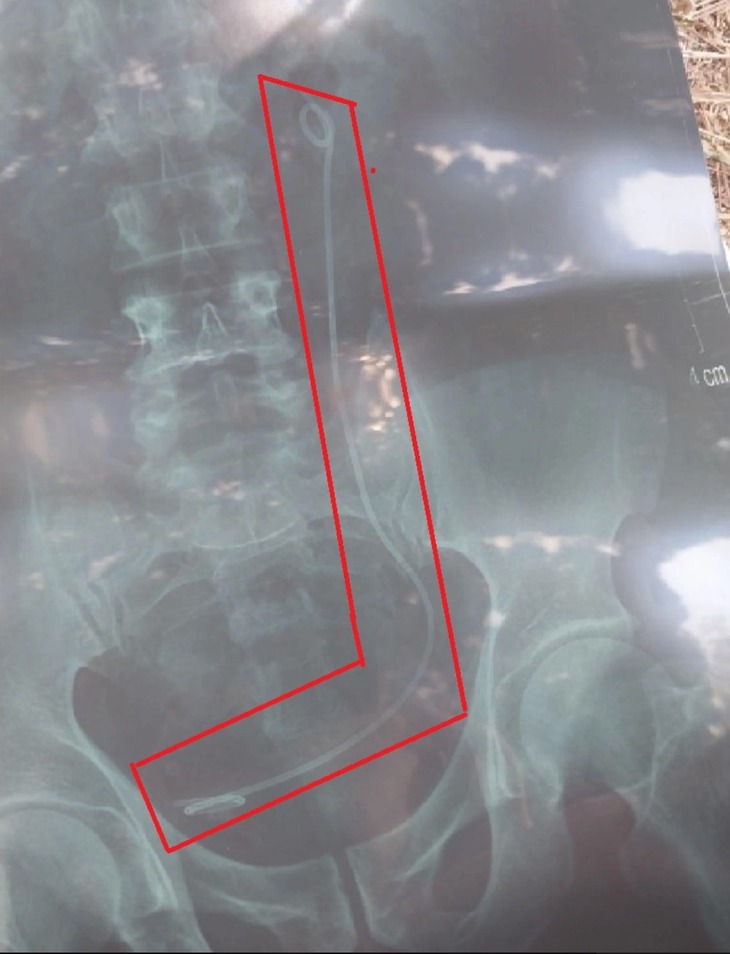

Tại đây, các bác sĩ đã yêu cầu bệnh nhân đi chụp X-quang. Sau khi nhận kết quả, các bác sĩ thông báo trong bụng ông H. có một sợi dây ống và tư vấn làm thủ thuật mổ nội soi để lấy sợi dây này ra.

Kết quả X-quang bệnh viện đưa nhầm cho bệnh nhân dẫn đến bệnh nhân bị mổ oan - Ảnh: T.A

Khi nhận kết quả chụp X-quang, ông H. rất ngạc nhiên và cho biết ông đã mổ thận trước đó và tái khám hằng năm nên không thể bất ngờ xuất hiện một sợi dây ống trong cơ thể. Tuy nhiên, sau khi nhận tư vấn của bác sĩ thì vợ chồng ông đồng ý mổ nội soi để lấy dị vật là ống nhựa trong bụng ra.

Theo Bệnh viện Đa khoa tỉnh Lâm Đồng, trong quá trình mổ thì phát hiện không có sợi dây ống trong bụng ông H.. Bác sĩ đưa ông H. chụp lại X-quang và phát hiện bộ phận chụp chiếu đã đưa nhầm kết quả của một bệnh nhân khác cho ông H..